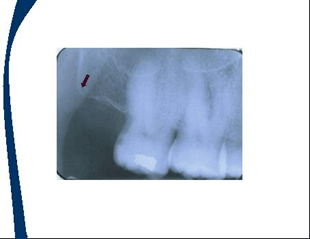

En las imagenes aparecen flechas que representan la localización de los landmarks o puntos de referencia

Punto de referencia Y invertida sobre el canino superior

Puntos de referencia de dientes posteriores maxilares

Seno maxilar

Hueso cigomatico